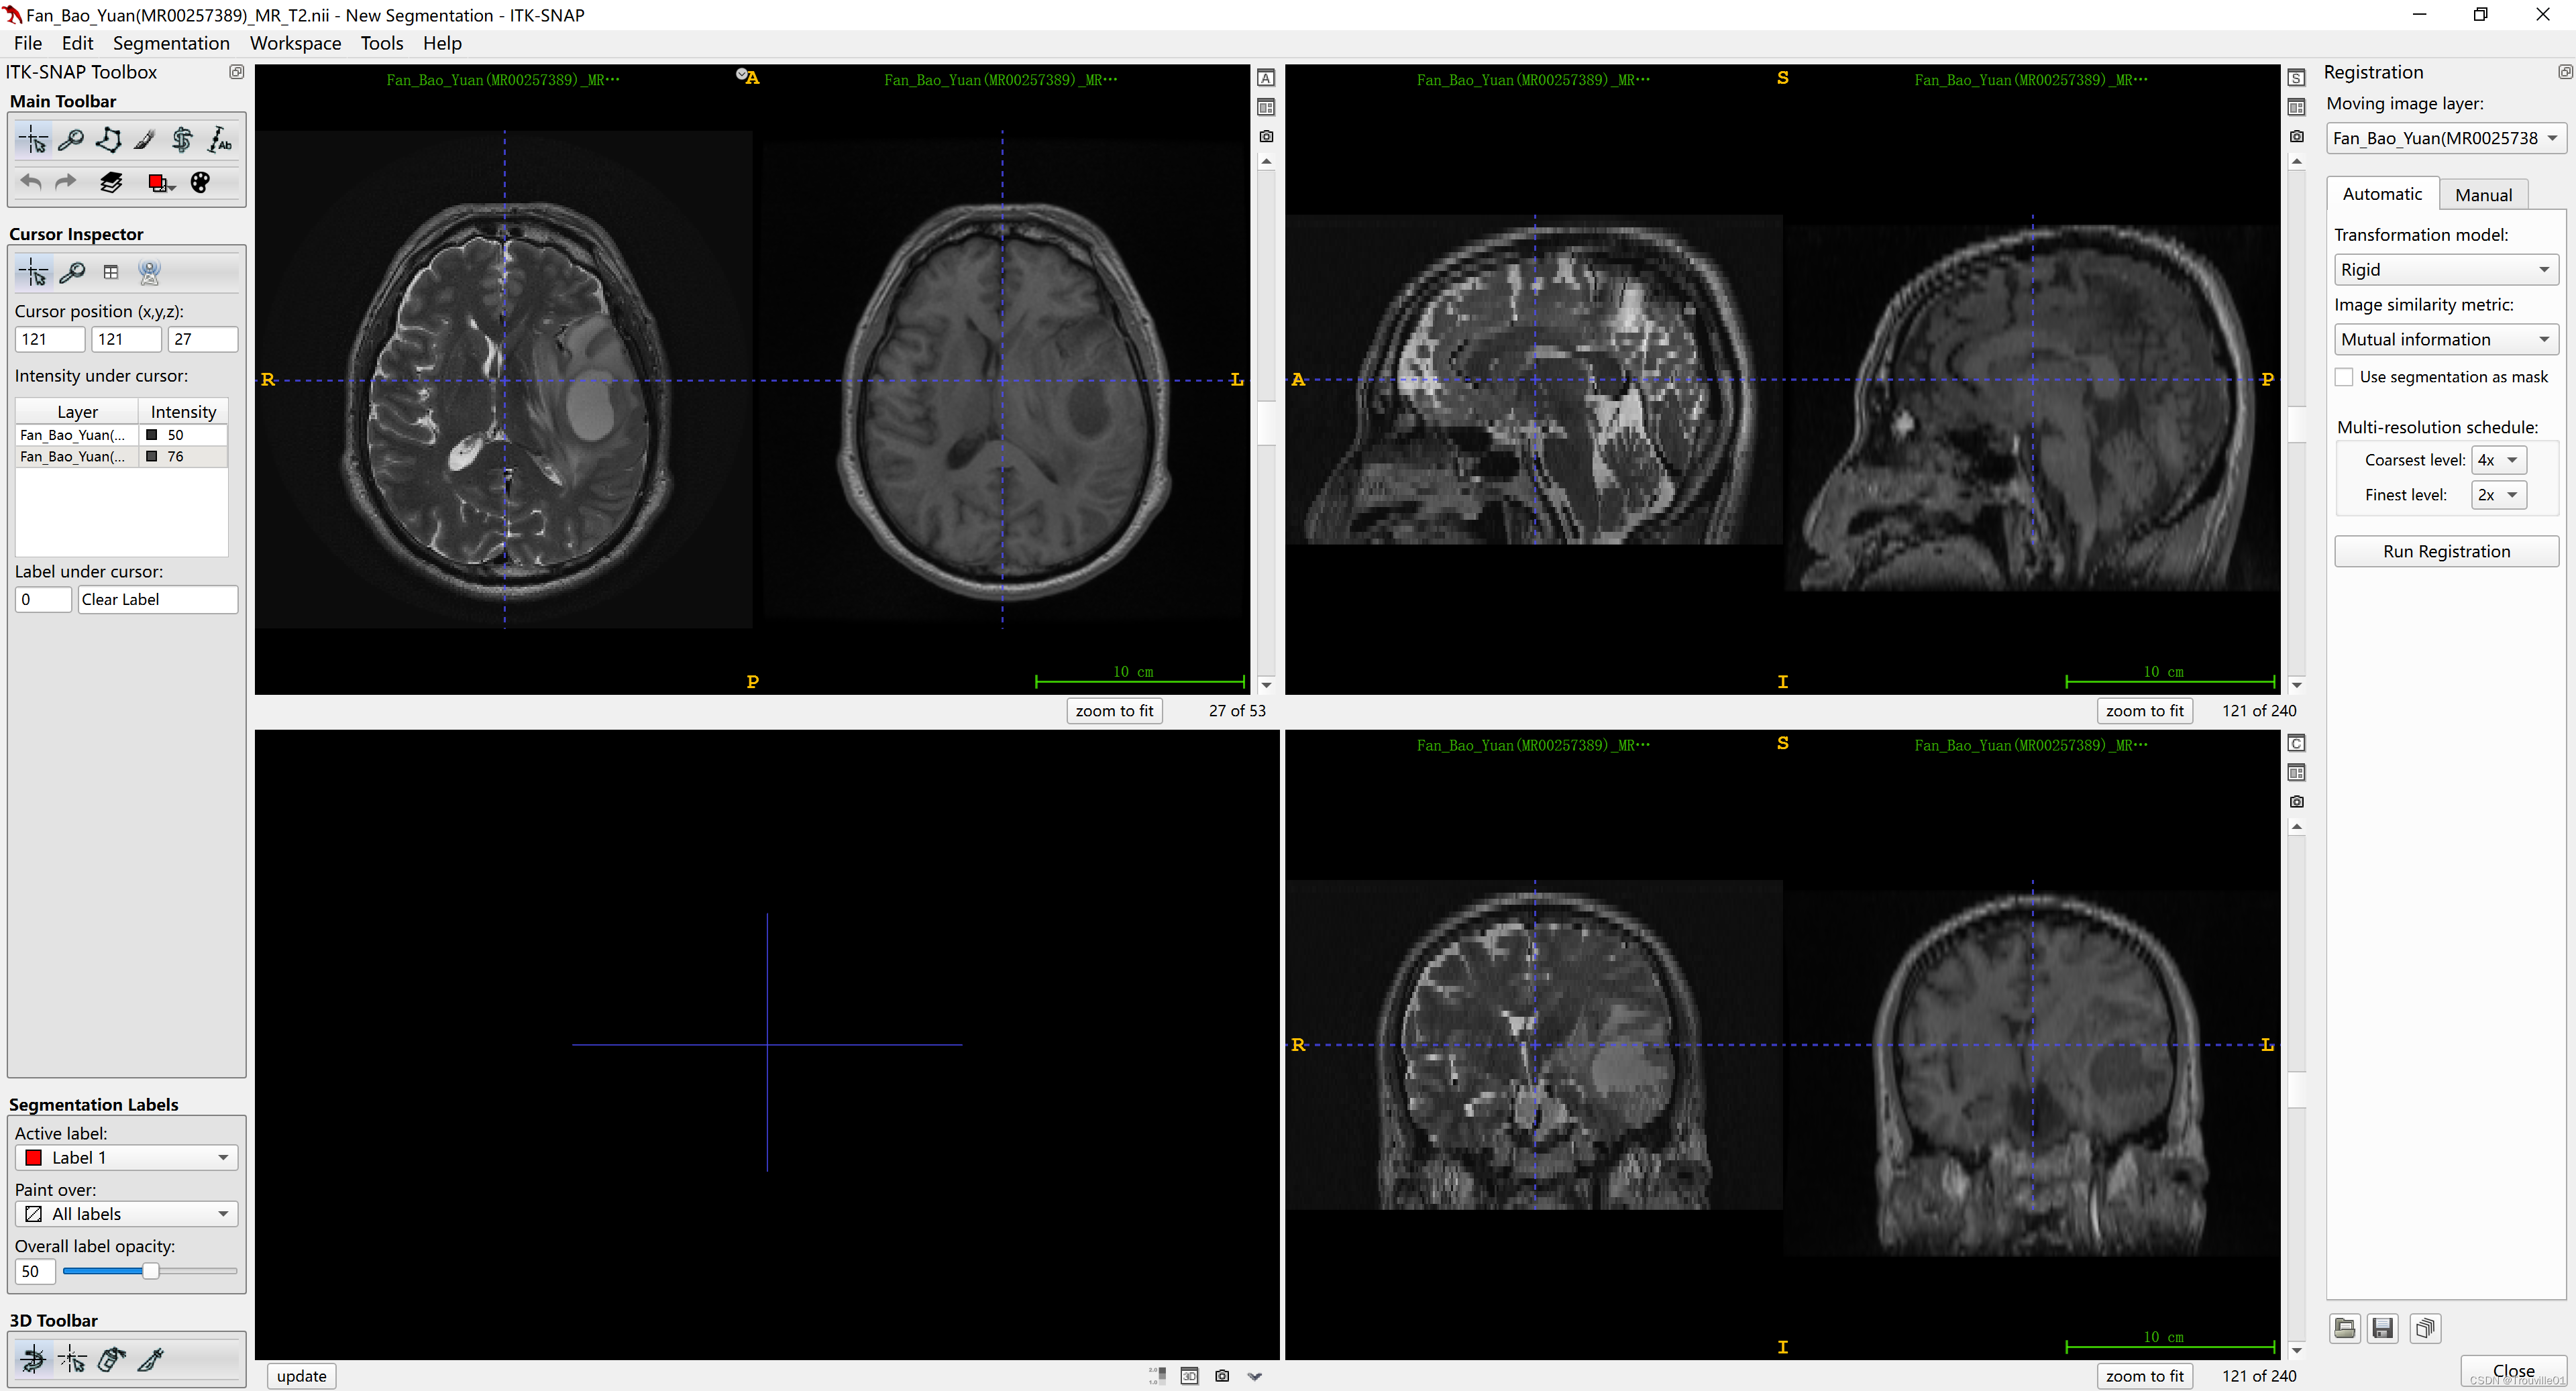

4. 点击tools,选择registration

5.选择右边菜单栏的Munal控件,选择Match by ,选择image centers,可以用来对齐图像,这步很关键!!!如果方向还是没有对齐,可以在图像上转动那个罗盘样的标尺来改变方向进行对齐。

6.选择automatic,run registration,到这里配准基本走完了,但是想要看到配准效果还得继续,